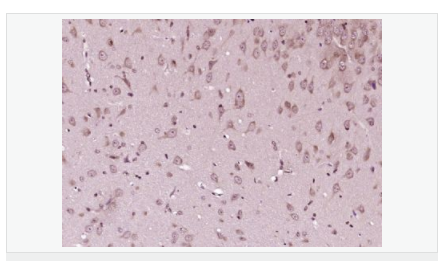

| 產(chǎn)品介紹 | This gene encodes a cyclin-dependent kinase inhibitor, which shares a limited similarity with CDK inhibitor CDKN1A/p21. The encoded protein binds to and prevents the activation of cyclin E-CDK2 or cyclin D-CDK4 complexes, and thus controls the cell cycle progression at G1. The degradation of this protein, which is triggered by its CDK dependent phosphorylation and subsequent ubiquitination by SCF complexes, is required for the cellular transition from quiescence to the proliferative state. [provided by RefSeq, Jul 2008] Function: Important regulator of cell cycle progression. Involved in G1 arrest. Potent inhibitor of cyclin E- and cyclin A-CDK2 complexes. Forms a complex with cyclin type D-CDK4 complexes and is involved in the assembly, stability, and modulation of CCND1-CDK4 complex activation. Acts either as an inhibitor or an activator of cyclin type D-CDK4 complexes depending on its phosphorylation state and/or stoichometry. Subunit: Forms a ternary compex with CCNE1/CDK2/CDKN1B. Subcellular Location: Nucleus. Cytoplasm. Endosome. Note=Nuclear and cytoplasmic in quiescent cells. AKT-or RSK-mediated phosphorylation on Thr-198, binds 14-3-3, translocates to the cytoplasm and promotes cell cycle progression. Mitogen-activated UHMK1 phosphorylation on Ser-10 also results in translocation to the cytoplasm and cell cycle progression. Phosphorylation on Ser-10 facilitates nuclear export. Translocates to the nucleus on phosphorylation of Tyr-88 and Tyr-89. Colocalizes at the endosome with SNX6; this leads to lysosomal degradation. Tissue Specificity: Expressed in all tissues tested. Highest levels in skeletal muscle, lowest in liver and kidney. Post-translational modifications: Phosphorylated; phosphorylation occurs on serine, threonine and tyrosine residues. Phosphorylation on Ser-10 is the major site of phosphorylation in resting cells, takes place at the G(0)-G(1) phase and leads to protein stability. Phosphorylation on other sites is greatly enhanced by mitogens, growth factors, cMYC and in certain cancer cell lines. The phosphorylated form found in the cytoplasm is inactivate. Phosphorylation on Thr-198 is required for interaction with 14-3-3 proteins. Phosphorylation on Thr-187, by CDK2 leads to protein ubiquitination and proteasomal degradation. Tyrosine phosphorylation promotes this process. Phosphorylation by PKB/AKT1 can be suppressed by LY294002, an inhibitor of the catalytic subunit of PI3K. Phosphorylation on Tyr-88 and Tyr-89 has no effect on binding CDK2, but is required for binding CDK4. Dephosphorylated on tyrosine residues by G-CSF. Ubiquitinated; in the cytoplasm by the KPC complex (composed of RNF123/KPC1 and UBAC1/KPC2) and, in the nucleus, by SCF(SKP2). The latter requires prior phosphorylation on Thr-187. Ubiquitinated; by a TRIM21-containing SCF(SKP2)-like complex; leads to its degradation. DISEASE: Defects in CDKN1B are the cause of multiple endocrine neoplasia type 4 (MEN4) [MIM:610755]. Multiple endocrine neoplasia (MEN) syndromes are inherited cancer syndromes of the thyroid. MEN4 is a MEN-like syndrome with a phenotypic overlap of both MEN1 and MEN2. Similarity: Belongs to the CDI family. SWISS: P46527 Gene ID: 1027 Database links: Entrez Gene: 1027 Human Entrez Gene: 12576 Mouse Omim: 600778 Human SwissProt: P46527 Human SwissProt: P46414 Mouse Unigene: 238990 Human Unigene: 2958 Mouse Important Note: This product as supplied is intended for research use only, not for use in human, therapeutic or diagnostic applications. P27蛋白是一種新發(fā)現(xiàn)的周期素依賴激酶抑制劑,屬于細胞周期的負(fù)性調(diào)控因子。P27基因及其產(chǎn)物的異常表達可能與某些腫瘤的發(fā)生、發(fā)展有著密切的關(guān)系。P27蛋白對細胞周期的調(diào)控及在腫瘤中發(fā)揮著很重要的作用。 |